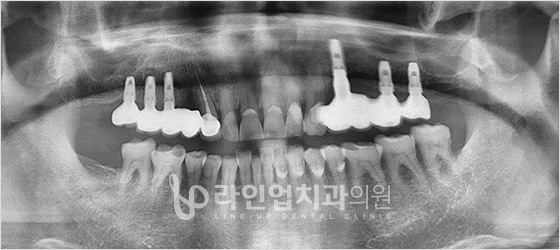

치료전

Before

치료후

After

앞니 임플란트 (42세/여/ 2015.09.14 ~ 2015/12.07)